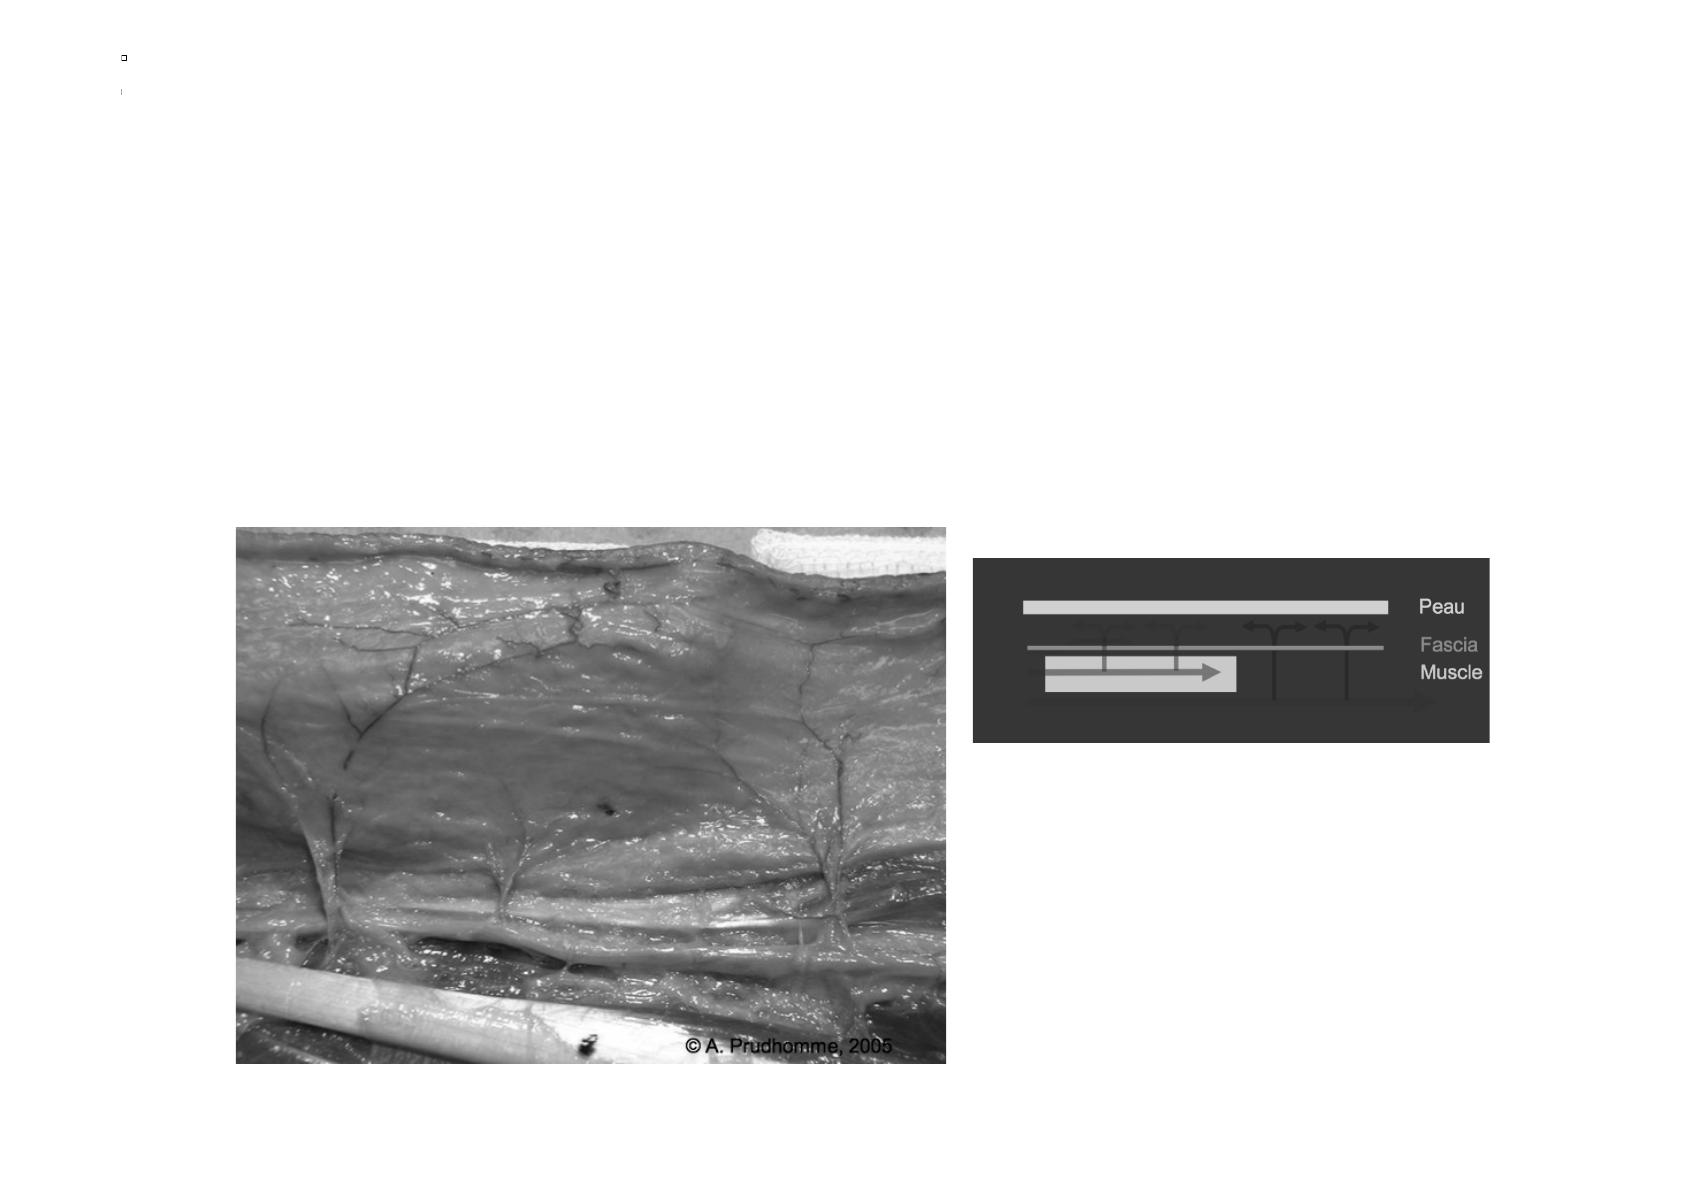

L’origine des hématomes disséquants et

des syndromes de Morel-Lavallée

Artère, veines et lymphatiques qui circulent entre fascia

des muscles et tissus cellulaire sous cutané

Photos Pélissier – Vascularisation des lambeaux - e-plastie